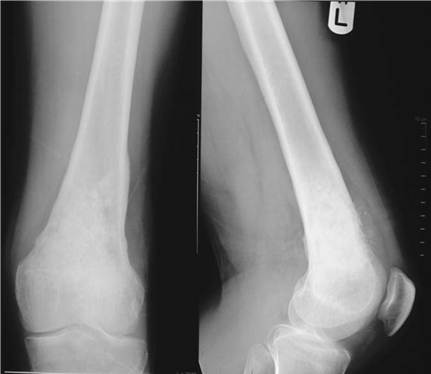

Describe the abnormalities you see on these radiographs. What is the likely diagnosis?

These AP and lateral radiographs show sessile lesions arising from the metaphyseal region of the distal femur. The lesions are well defi ned and appear to be growing away from the metaphysis. The matrix of the lesions is in continuity with the surrounding normal bone. The cortex of the normal bone appears to be in continuity with the lesions. The caps of the lesions contain fl ecks of calcifi cation. These appearances would be compatible with a slow-growing, benign lesion, most likely osteochondroma.

What is the inheritance pattern and natural history of this disease. What sites are commonly aff ected?

Hereditary multiple exostoses (HME) is a familial inherited autosomal dominant condition but spontaneous mutation also occurs. Males are more often aff ected, possibly due to an incomplete penetrance in females. Three gene mutations have been identifi ed that can lead to HME. HME Type I is caused by a mutation in the gene encoding exostosin-1 ( EXT1) which maps to chromosome 8q24. HME Type II is caused by mutation in the gene encoding exostosin-2 ( EXT2 ), on chromosome 11, and HME Type III has been mapped to a locus on chromosome 19 ( EXT3 ). There is some evidence for an additional multiple exostoses locus. The condition has an estimated incidence of 1 in 50,000.

Exostoses may be present at birth โ over 80 % of patients are diagnosed in the fi rst decade of life (median age 3 years). There may be a few or hundreds of lesions present and the number and size tends to increase with growth.

The radiographic distribution of lesions is as follows: z Distal femur 70 % z Ribs 40 % z Proximal tibia 70 % z Distal radius 30 % z Proximal humerus 50 % z Distal ulna 30 % z Scapula 40 %

What clinical problems does it cause?

Generally, patients present with a painless mass. The developing exostoses may lead to abnormalities in osseous growth, joint restriction, joint deformities particularly aff ecting paired bones, and early progression to osteoarthritis.

Lesions that continue to enlarge after the end of puberty are abnormal and should be investigated for potential malignant change (chondrosarcoma). Ultrasonography and MRI are usually the investigations of choice.

Features suggesting malignant change include:

z Increasing pain and swelling (especially after cessation of normal growth) z Thickening of the cartilage cap ( > 2 cm is very concerning) z Lysis of a proportion of the stalk z Intramedullary invasion of the underlying bone